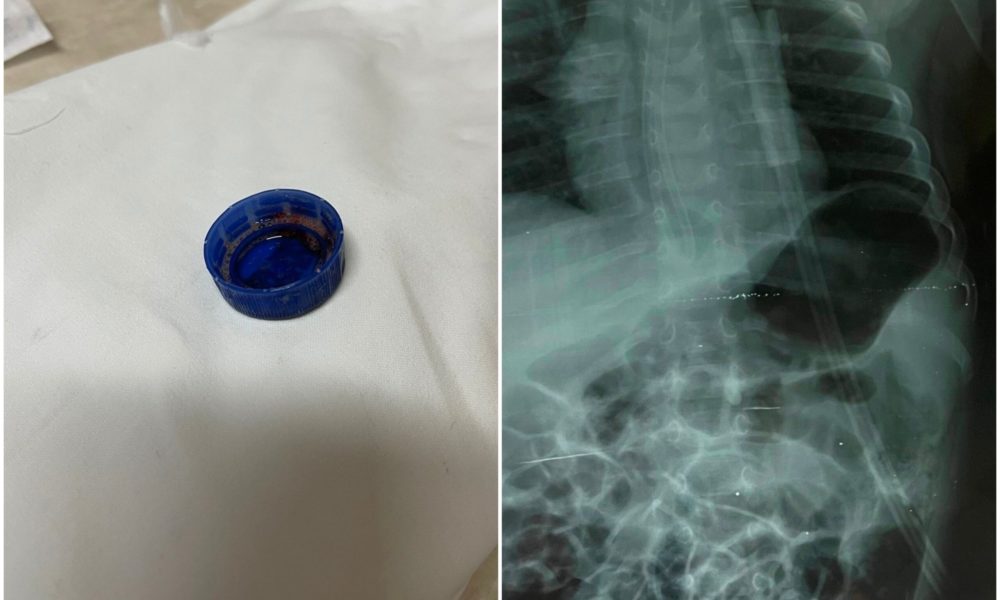

Chișinău: Un copil se zbate între viață și moarte, după ce a căzut în gol de la etajul 8 al unui bloc de locuit